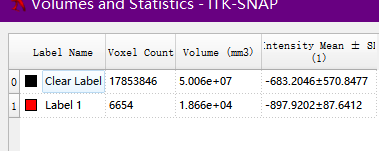

Volumes and Statistics获取空间的统计数据